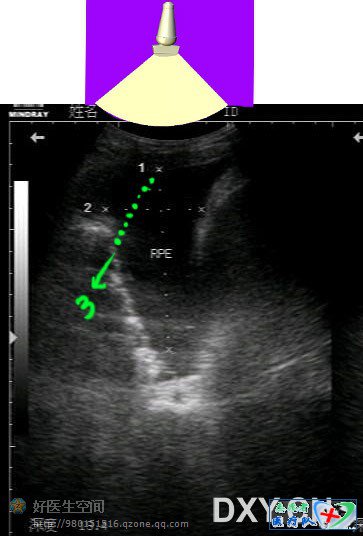

现在我把图转90度竖起来,恢复B超报告排版样式,顺便纠正一条线,亲们都看懂了吗?没看懂请举手